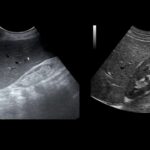

Um exame de sangue que mede a creatinina pode indicar se seus rins estão funcionando adequadamente. Se os níveis de creatinina estiverem elevados, isso pode indicar que seus rins não estão filtrando corretamente. Além disso, a presença de proteína na urina ou alterações no exame de imagem dos rins também podem indicar a presença da doença renal crônica.